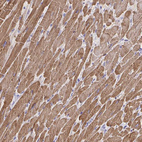

Immunohistochemistry analysis in human heart muscle and liver tissues using HPA017888 antibody. Corresponding TNNT2 RNA-seq data are presented for the same tissues.